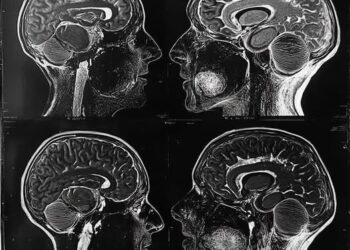

Agjërimi, si një praktikë që fton trupin të rigjenerohet dhe mendjen të rifitojë kontrollin

Agjërimi shpesh perceptohet vetëm si një akt devocioni dhe sakrifice në kuadër të praktikave fetare. Megjithatë, përtej simbolikës shpirtërore, ai ...